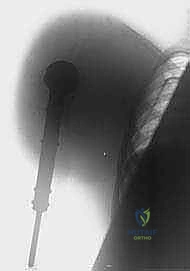

الخطوة 3: التعامل مع عظم الترقوة (Clavicle Osteotomy)

يتم كشف عظم الترقوة وقصه (قطعه) من المنتصف أو بالقرب من مفصل القص. هذه الخطوة "تفتح الباب" للوصول إلى الهياكل الحيوية العميقة.

الخطوة 4: السيطرة على الأوعية الدموية والأعصاب (الخطوة الأهم)

هنا تتجلى خبرة الدكتور هطيف في الجراحة الميكروسكوبية. يتم كشف الشريان والوريد تحت الترقوة (Subclavian Artery and Vein). يتم ربط هذه الأوعية الدموية الكبيرة وقطعها بحذر شديد لمنع أي نزيف مميت. بعد ذلك، يتم تحديد الضفيرة العضدية (Brachial Plexus) - وهي حزمة الأعصاب الرئيسية - ويتم حقنها بمخدر موضعي قبل قطعها لتقليل صدمة العصب والحد من "ألم الطرف الوهمي" مستقبلاً.